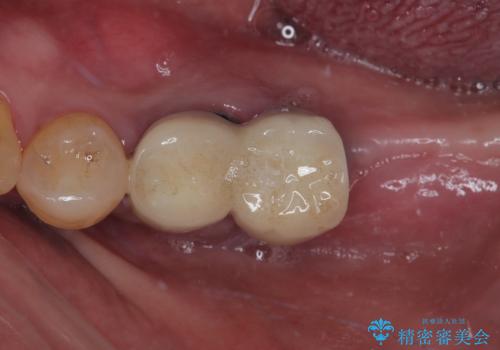

- 連結されている奥歯がグラグラしていて、インプラント治療を希望して来院された患者様です。

連結の手前の歯は歯根が破折して、クラウンが歯から外れており、奥の歯は動揺により歯根周辺の骨が吸収している状態でした。

骨吸収が甚大な後方は3ヶ月ほど待機して、手前は抜歯即時埋入により、短期間インプラント補綴治療を行うこととしました。